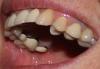

Bukasha Опубликовано 24 мая, 2011 Поделиться Опубликовано 24 мая, 2011 Здравствуйте.Неск. дней назад мне поставили восемь коронок мк на постоянный цемент. И я увидела, что внутри на всех коронках темные полоски. Для меня это стало сюрпризом, честно говоря. Врач сказал, что изнутри не видно. Видно конечно, ещё как, особенно если учесть, что по роду работы у меня часто и широко открыт рот, причем при большом количестве людей. И у коллег многих видно всё-всё во рту. Вобщем понятно, что эстетика не айс. Я узнала из инета, что это называется "гирлянда". И что есть ещё такая "плечевая масса". А теперь собственно вопрос: зачем это сделано, можно ли (было) избежать, как оцениваются такие коронки: как гирлянды или как с плечевой массой, если со стороны щек у них нет темных полосок, а со второй стороны есть. Я нашла тут тему о похожем, но честно - не поняла из ответов врачей, зачем нужны эти гирлянды. Для здоровья ли дёсен, для экономии средств пациента, для экономии времени техника или это сложная технология - выводить плечевые массы? Если десна поднимется "с годами" и станет серой, так там уже чЁрно!))...Я в глубоких раздумьях. Ссылка на комментарий

Bukasha Опубликовано 31 мая, 2011 Автор Поделиться Опубликовано 31 мая, 2011 (изменено) Делаю гирлянду практически всегда,единственное,предупреждаю заранее.Альтернатива-светлая гирлянда на коронках из оксида циркония с ценником ,начинающимся от 20 тысяч за коронку в зависимости от региона (ну и до 60 ).Под плечевую массу обтачивать зуб по кругу бывает просто невозможно,столько тканей твёрдых просто нет,ну или негуманно,чем больше останется зуба,тем лучше ретенция(удержание) коронки,эстетика эстетикой,ну и функция должна быть обеспечена ,вы же жуёте коронками ,не только улыбаетесь,а нагрузка колоссальная при жевании,не забывайте,тысячи циклов жевательных она обязана вам обеспечить.В общем ,не знаю,что надо делать на работе,чтобы коллеги увидели гирлянду на молярах,уж извините. Сцена, софиты, хор, солисты... Оперный театр. Зрителям не видно, коллегам видно. Смотрите, на втором фото никаких расширителей, просто открыла рот, запрокинула слегка голову, муж сфоткал со вспышкой. Ладно, это уже, оказывается, полбеды. Вы очень нужный вопрос затронули, про тысячи жевательных циклов. Новую тему наверное не надо мне создавать, здесь расскажу. Я не могу жевать на одной стороне. Точнее, мне тяжело это делать, как будто там не хватает высоты. Сегодня была на проверке-коррекции, бумажечками синеньками мне показывали, что "контакт есть, всё хорошо". А мне - нехорошо...(( Обыкновенный ужин вызывает усталость, как будто челюсти ходили в тренажерный зал. Если пища справа - нормально, если слева - как будто перетираю её. Три раза он мне этот мост (5-6-7) переделывал в общей сложности. Когда первый раз пожаловалась на неполный контакт - переделал ещё ниже, даже визуально было заметно, сам согласился. И я с ними долго ходила, пока другими зубами занималась, как с времянками... А контакт сегодня синей краской был не по всей шестёрке (меня она беспокоит больше всего ), а как-то по диагонали. Как самой проверить? Или не самой, но объективно? Я уже сходила к ортодонту в гос. клинику, он видел и предыдущую заниженную работу. Сказал - теперь есть контакт, хороший везде. А я как тупая мельница чувствую себя. Там даже форма какая-то допотопная по жевательной поверхности: плоские лепешки со вмятинками. Что делать?.. Изменено 31 мая, 2011 пользователем Bukasha Ссылка на комментарий